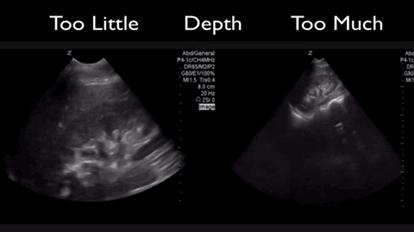

QA of the Day, Sono Stuff QA of the Day – Depth. 1-2 cm of additional depth best. #pocus #foamed #foamus #meded Date: July 21, 2016Author: Mike 0 Comments Too much or little depth and you can miss important findings. Share this: Share on X (Opens in new window) X Share on Facebook (Opens in new window) Facebook Like Loading...